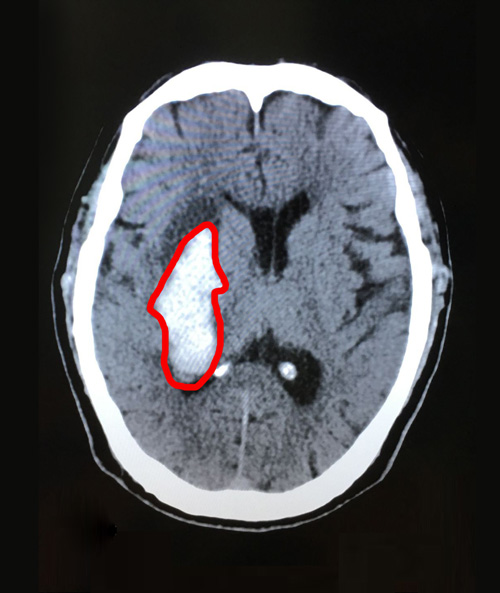

检查结果出来后,右侧基底节区脑出血,出血量一度达到35毫升,非常危险!

术前影像:右侧基底节区急性脑出血,右侧脑室后角少量积血